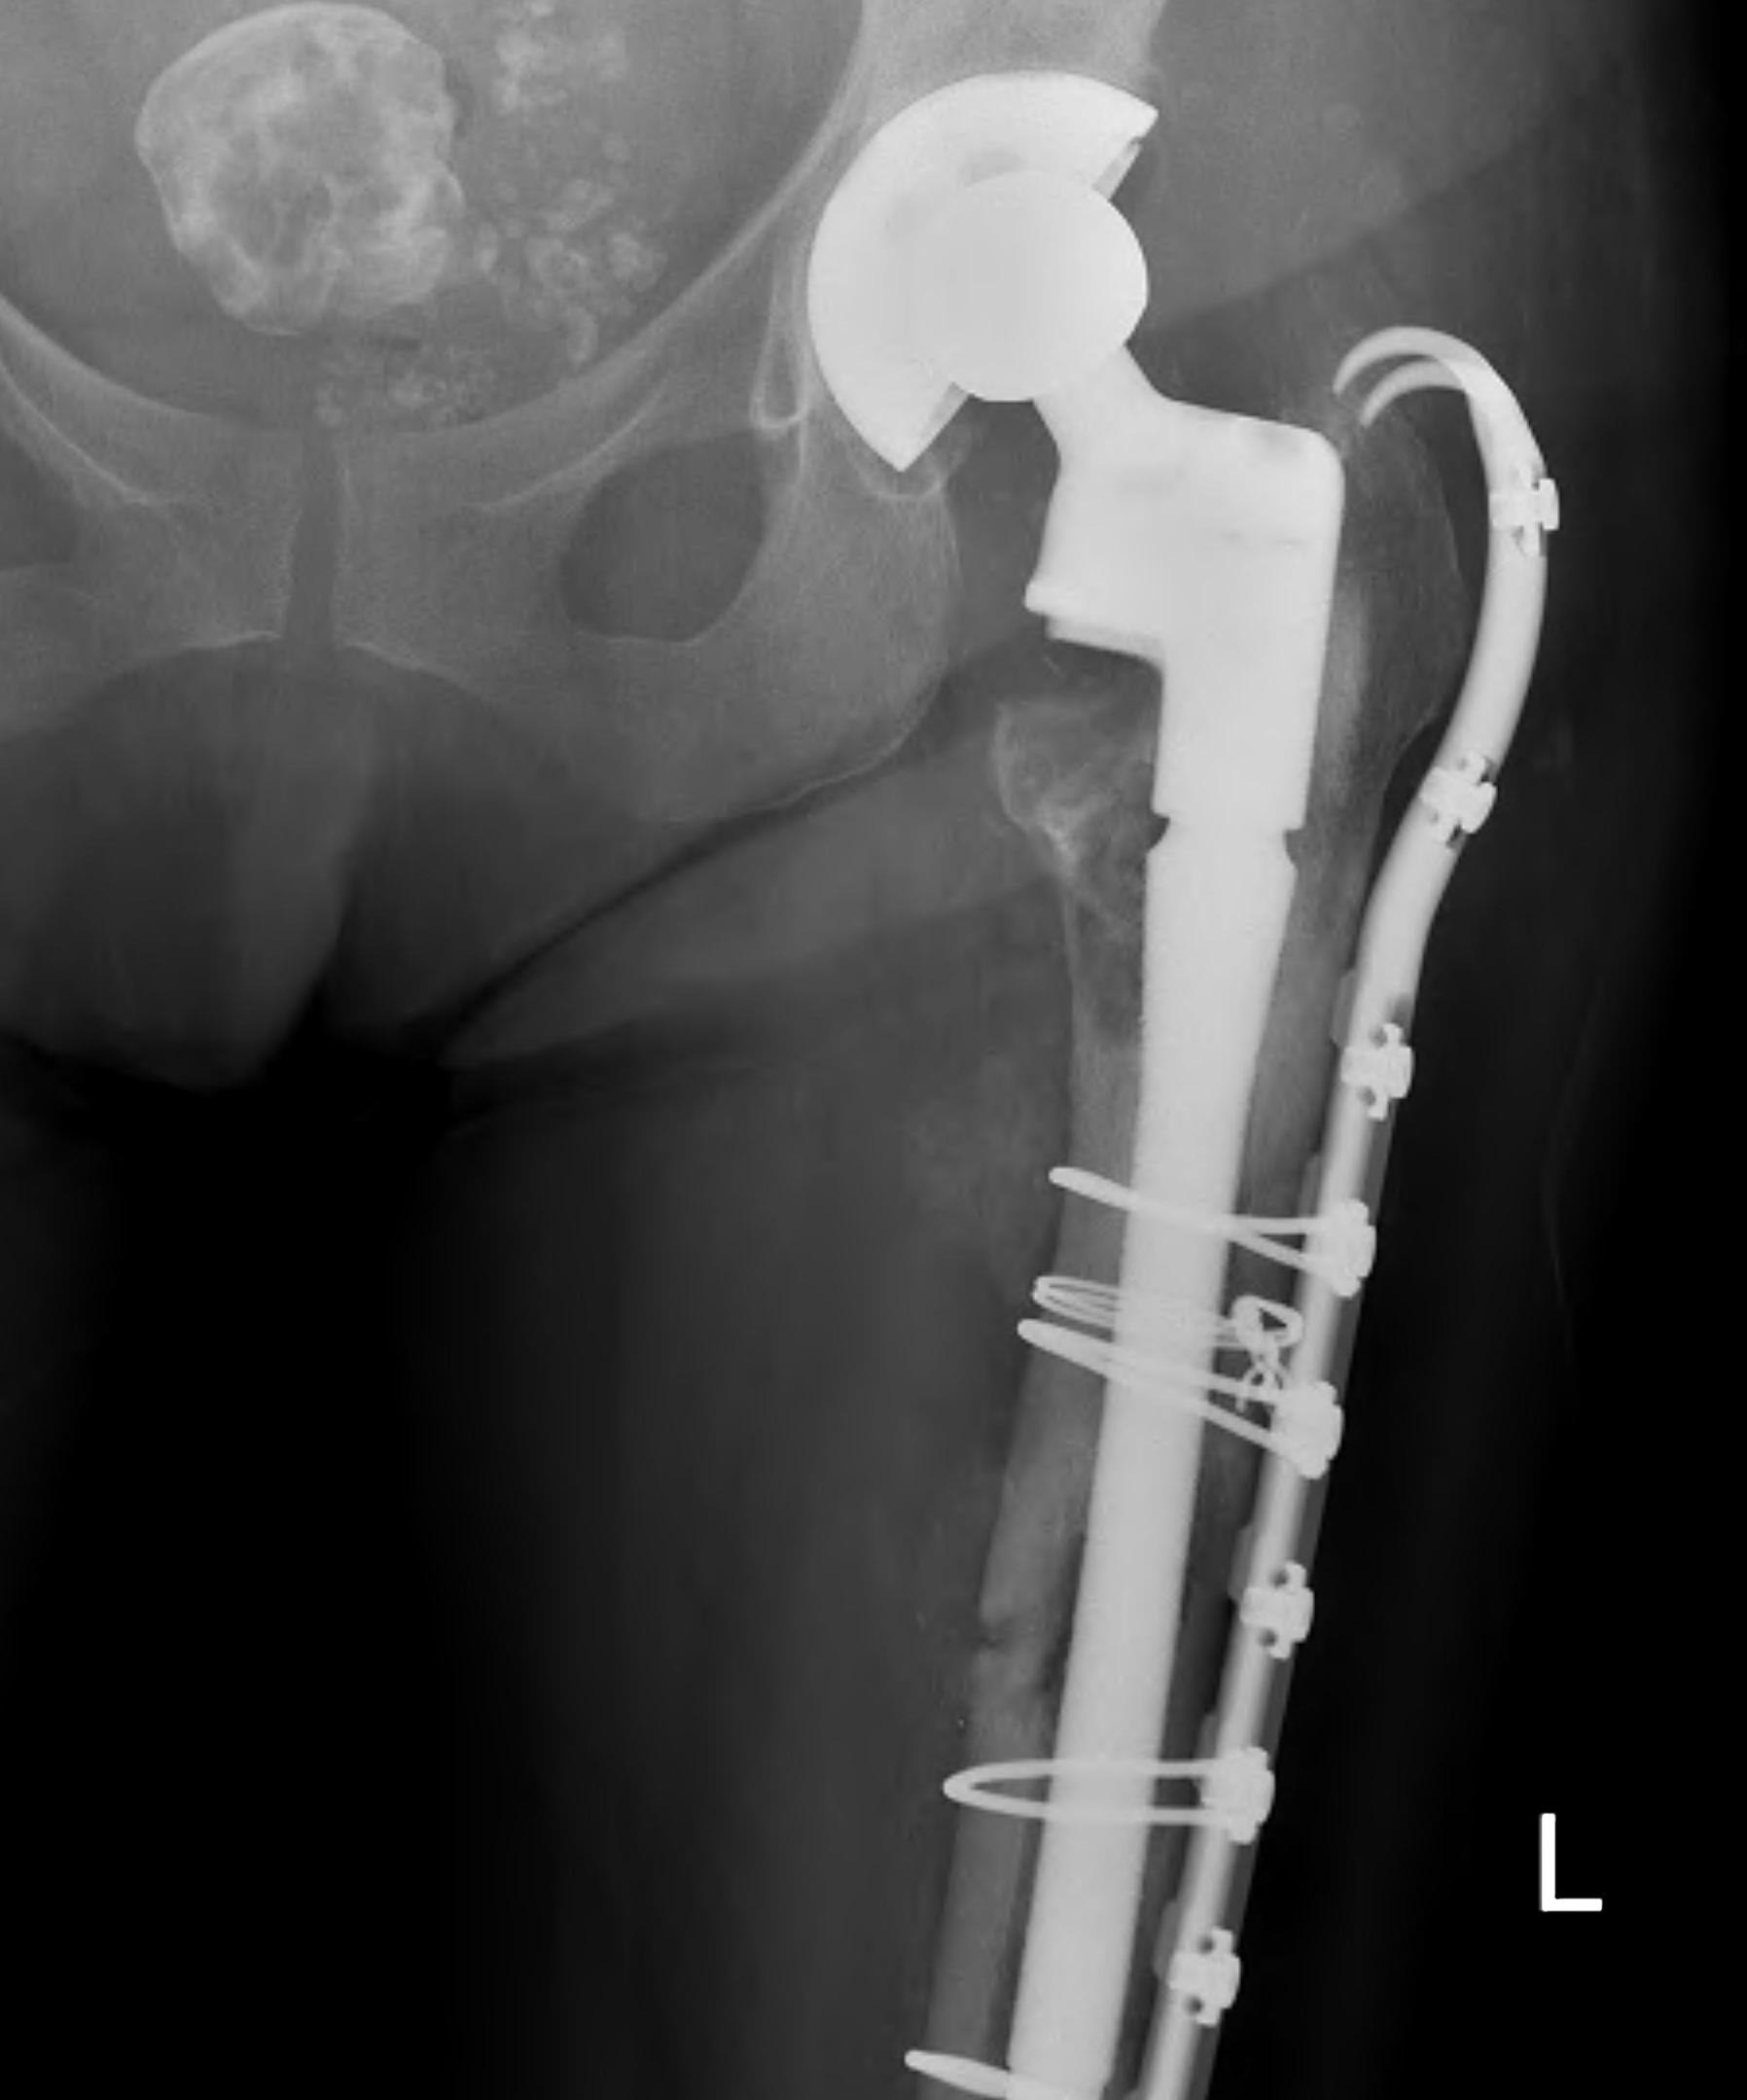

Long stem uncemented revision with cortical strut allograft

Long stem uncemented revision with plate + cortical struts

- long stem modular revision implants +/- plate +/- cortical strut